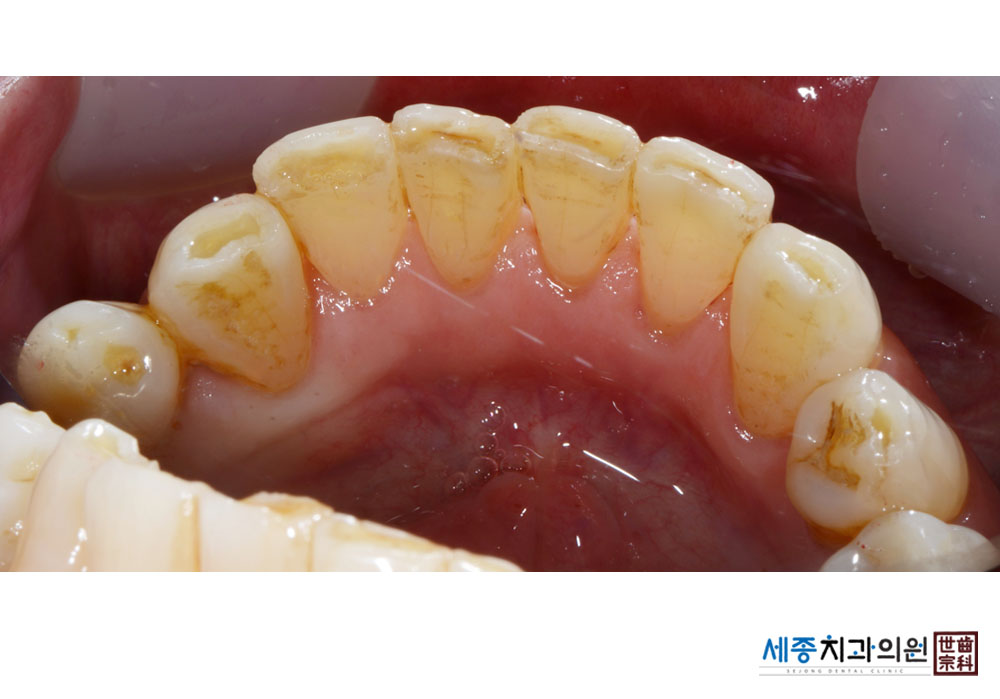

[스케일링] 치주질환 예방 스케일링

치료전 : 2021-09-23

가글마취&저주파 스켈러를 사용한 스케일링